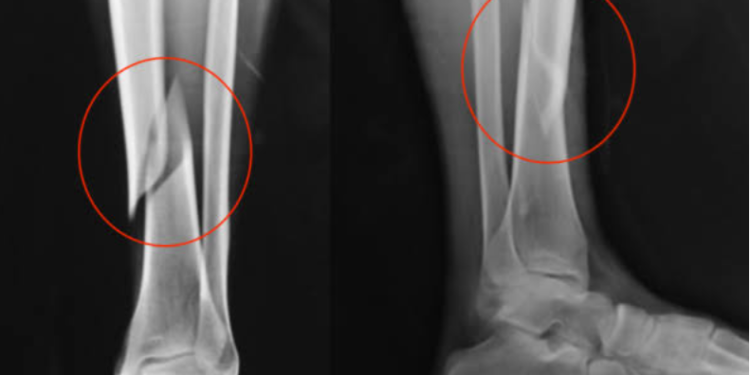

Um raio-X mostra duas fraturas nas pernas da candidata, que segundo informações de outros candidatos estava quase finalizando o teste quando o acidente ocorreu. A cerca de 200 metros a tíbia quebrou e ela foi ao chão.